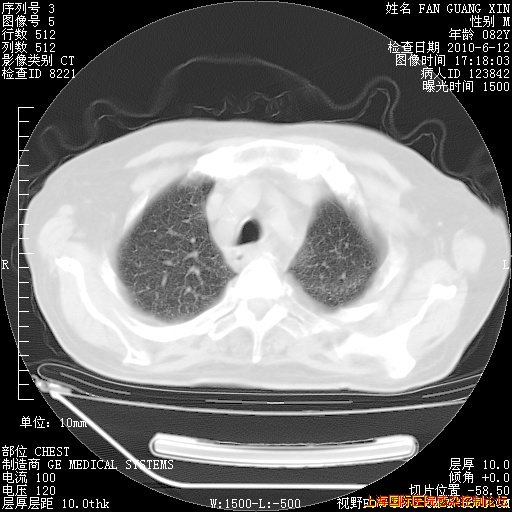

补发6月12日肺部CT肺窗

6月12日肺窗

整整相隔30天的肺部CT好像有所好转啊。甲强龙减量第3天,需要观察体温。

海管,自昨日你和我通完话后,不知您岳父消化道症状有无缓解?体温怎样?阅读7.12日胸部ct,个人认为目前激素治疗是有效的,甲强龙减量是适宜的。因在抗痨治疗,需密切观察肝功、肾功能和血常规。不过,老年、长期住院和大量使用激素,很担心菌群失调发生